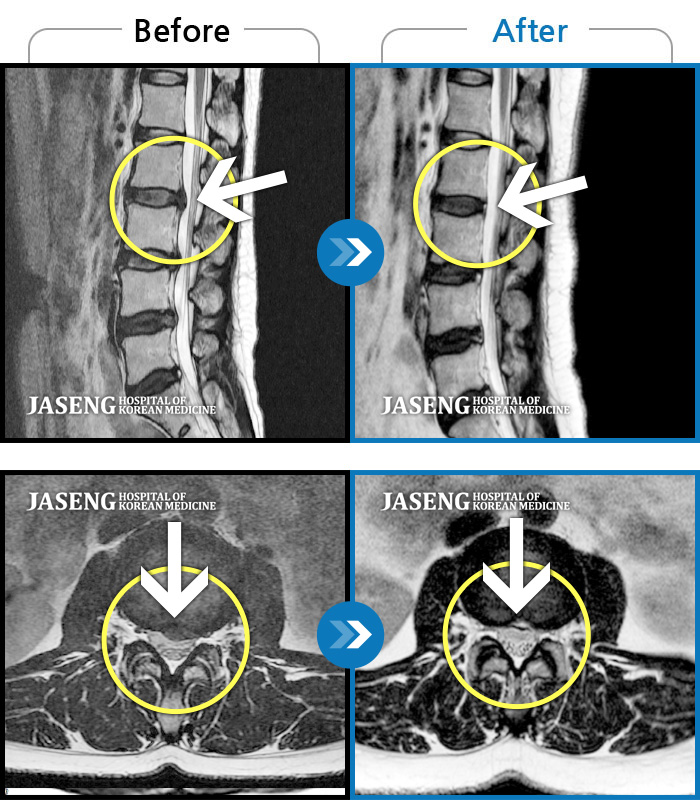

MRI 결과는 추간판협착증 2군데와 추간판탈출되어 터져서 디스크가 좌측으로 흘러내려 좌측 신경을 넓게 누르고 있는 곳이 1군데로 예상보다 심각한 상태였더군요.